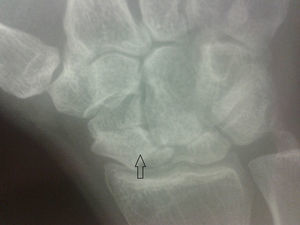

La radiografía de los carpos mostró rarefacción ósea en ambos escafoides, con esclerosis marcada y fenómenos degenerativos graves (fig. 1), lesión que se confirmó en la resonancia magnética (RM). Estos hallazgos eran compatibles con osteonecrosis (ON) bilateral de dicho hueso, por lo que se realizó diagnóstico de enfermedad de Preiser bilateral idiopática, al no encontrarse patología asociada (fig. 2A y B).